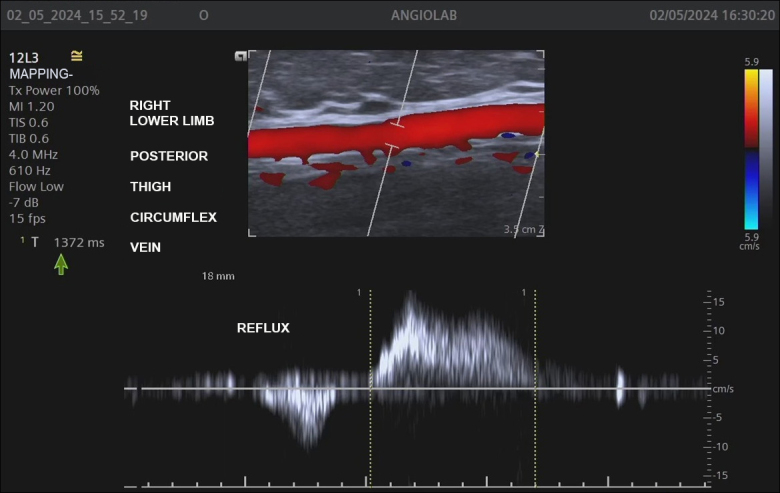

Background: The Giacomini vein (GV) can transfer reflux from perineal veins, tributary veins, and perforators of the thigh to the small saphenous vein (SSV). Vascular ultrasound with Doppler (VUD) is the preferred method for detecting reflux in specific veins such as the GV.

Objective: To identify GV depth and diameter, reflux in the GV, and presence of reflux in the SSV caused by the GV.

Methods: A cross-sectional, retrospective study was conducted in women undergoing lower limb venous mapping for varicose vein surgery. The following parameters were analyzed in GVs in which reflux was detected: segmental or diffuse reflux pattern; GV diameter and depth; and reflux in the SSV caused by the GV.

Results: 340 of the 2368 women evaluated were included in the study because they had a GV, totaling 511 veins analyzed, 150 (29.4%) of which had reflux. The diameters of the 150 GVs with reflux ranged from 1.5 to 7.8 mm and their depth varied from 4 to 25 mm. Most GVs with reflux (91.3%) had a segmental reflux pattern. The majority (66%) of refluxing GVs drained reflux into the popliteal vein through the saphenopopliteal junction, while reflux was transferred to the SSV in 34 veins (22.7%), and was drained by a tributary vein in the thigh in 15 veins (11.3%).

Conclusions: Approximately one-third of the studied GVs had reflux, mostly segmental, mean caliber was 2.7 mm, and mean depth was 11 mm. Reflux in the SSV originating from the GV was detected in 22% of the evaluated veins.